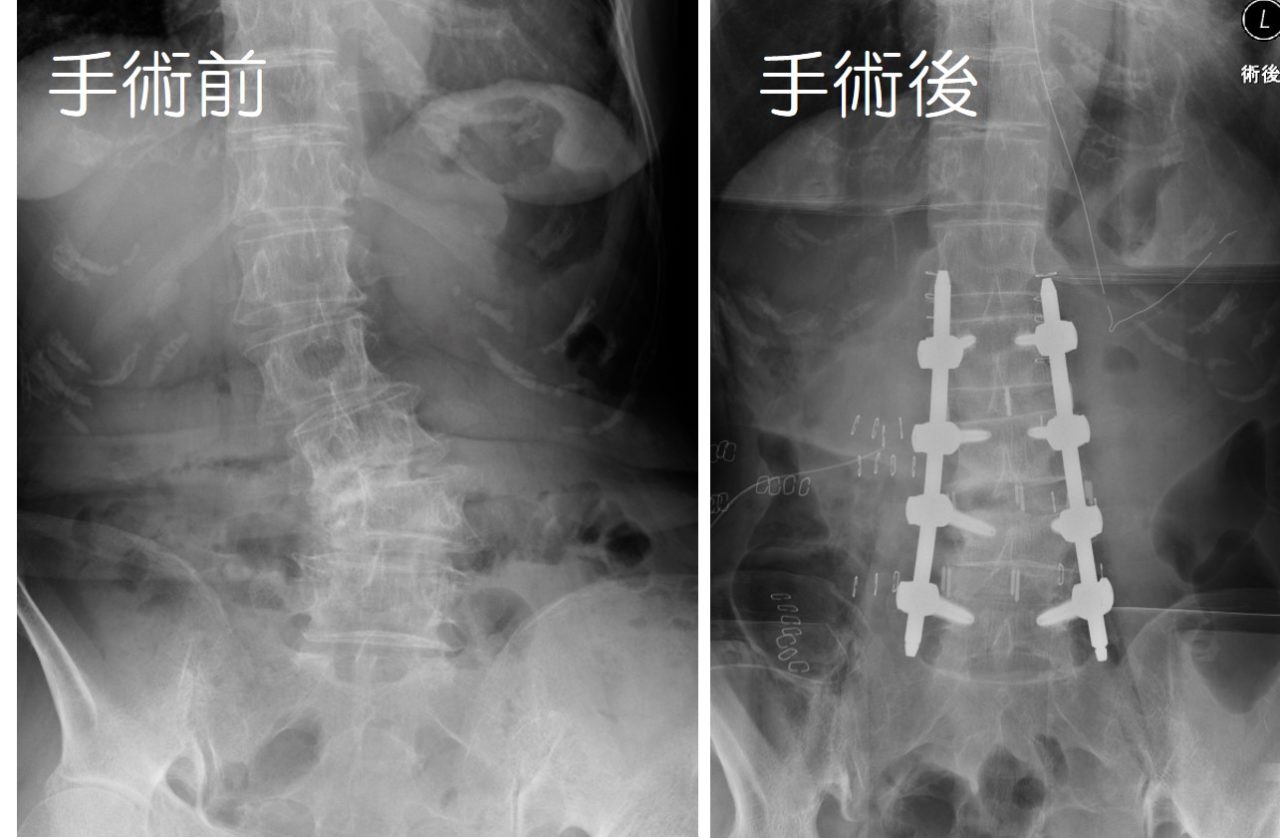

【変性側弯症に対する矯正固定術】

脊椎固定術は、脊椎の不安定性が強い場合や変形に対して矯正(きょうせい:良い形に戻すこと)する場合、そのほかにも固定をすることによって症状の改善が期待できる場合(一部の腰痛など)に対して行います。

通常、金属のネジを背骨(せぼね)に挿入して、そのネジを金属の棒で連結して固定します。